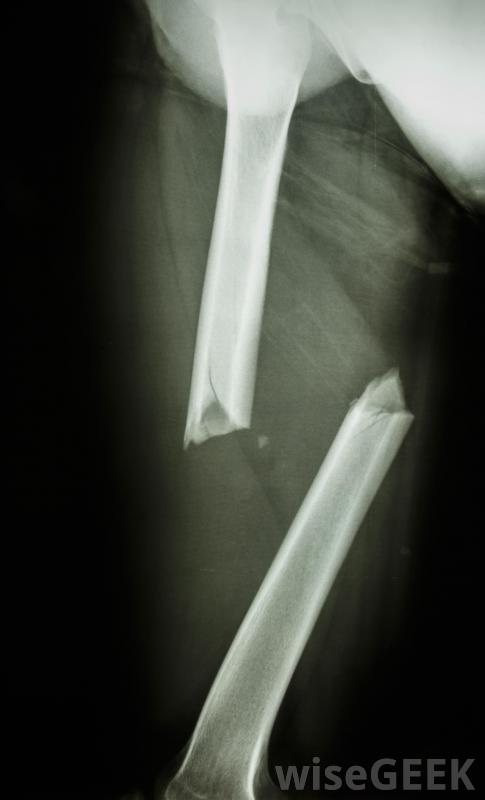

內固定術是一種治療骨折的方法,骨科醫生將設備植入骨內或骨旁,然后關閉手術部位,為體內骨骼的愈合提供支持,而不是像石膏一樣使用外固定器。這種治療方法在19世紀中葉開始出現,并且可以通過縮短愈合時間,使患者更舒適,并提供骨折的直接強化,使其更容易正常愈合,從而改善患者的預后。如果這是一個病人的選擇,外科醫生通常會推薦將病人帶到手術室進行全身麻醉進行內固定,內固定可使用多種器械,包括螺釘、釘子、桿、板,別針,外科醫生將利用像X光片這樣的醫學影像學研究來了解骨折的性質,并制定一個有效和適當的治療方案。這包括準備好內固定裝置,以便為手術做好準備。病人被帶進手術室,接受全身麻醉這樣外科醫生就可以進入手術部位,安裝設備,然后閉合傷口。內固定有助于骨折正常愈合這通常是外科手術中被稱為開放復位內固定(ORIF)的一部分。"開放復位"是指打開病人的身體,讓他們清楚地看到骨折,然后把骨頭放回原位,而不是閉合復位,骨科醫生保持皮膚完好無損,通過操縱該區域的骨骼將骨折固定到位。骨折的外科矯正更具侵略性,但也可以更精確。患者通常可以在手術后幾天內舒適地淋浴內固定術后患者通常能很快活動,但不應因劇烈的體力活動而使骨折部位勞損,可能需要吊帶或拐杖,由于缺少石膏,骨折的護理變得更加容易。患者通常可以在手術后幾天內舒適地洗澡,也會發現穿衣服和執行其他基本功能更容易。如果外科醫生批準,他們可以在骨骼完全愈合之前開始物理治療,以改善該區域的肌肉健康這一點。內固定可用于支持膝關節骨的愈合內固定的一個常見風險是手術部位感染,包括固定裝置上的細菌或霉菌定植。麻醉也有風險,尤其是那些經歷過嚴重創傷(如車禍)的患者,其穩定性可能會降低。此外,骨骼也有可能無法正常愈合,需要另一次手術來糾正問題。患者可能會選擇將設備留在原位,在這種情況下,他們可能會在安全檢查站遇到問題;他們也會一旦骨完全愈合并穩定,可將其取出。骨折有時需要外科手術來重新排列骨骼并將其固定到位內固定后,拐杖可以減少骨折部位的應力。